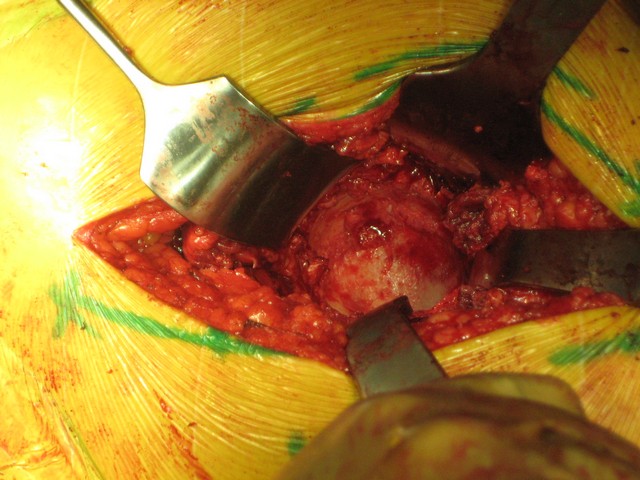

таз оказался стабильным, Corail-Duraloc, с пластикой дна.